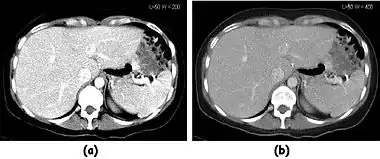

![]() Fig. 7.15.2: Effect of window width and level on CT image display: (a) Level = 50; Width = 200. (b) Level = 50; Width = 400. The image in (a) is displayed with greater contrast and appears noisier than that in (b). | ![]() Fig. 7.15.3: Effect of window width and level: (a) Level = -600; Width = 1700. (b) Level = -60; Width = 400. Image (a) displays the lung tissue more clearly, while image (b) can be used to highlight any pulmonary lesions. |

- Examples of image display manipulation are shown in the two figures above. In Figure 7.15.2, the same image of a slice through a patient's liver is displayed using a relatively narrow window (high contrast) and also with a wide window. The image with the narrower window appears noisier, but this is merely a reflection of the fact that the gray scale is spread over a narrow range of CT-numbers.

- Figure 7.15.3 illustrates the use of a relatively narrow window to highlight pathology in the lungs.